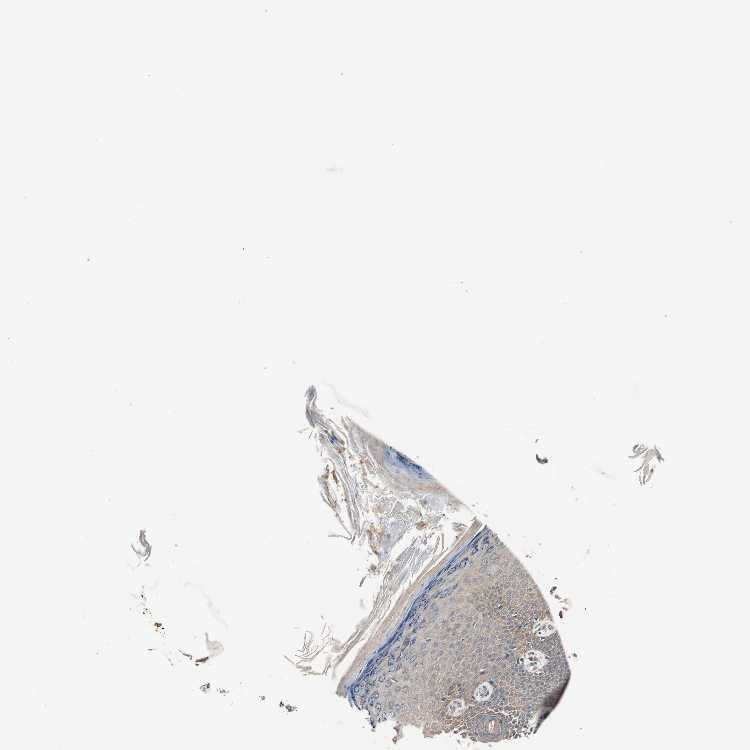

SKIN 1 - Antibody stainingi

Antibody staining in the annotated cell types in the current human tissue is reported as not detected, low, medium, or high, based on conventional immunohistochemistry profiling in selected tissues. This score is based on the combination of the staining intensity and fraction of stained cells.

Each image is clickable and will lead to virtual microscopy that enables deeper exploration of all samples and also displays staining intensity scores, fraction scores and subcellular localization as well as patient and tissue information for each sample.

Antibody HPA006804

Langerhans Not detected

Fibroblasts Medium

Keratinocytes Low

Melanocytes Low